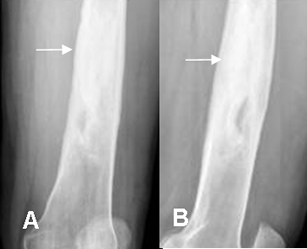

Fig 42. Osteomielitis crónica.

Rx AP. Area radiolúcida en la metáfisis femoral, con lesión sólida en su interior, que corresponde a secuestro.